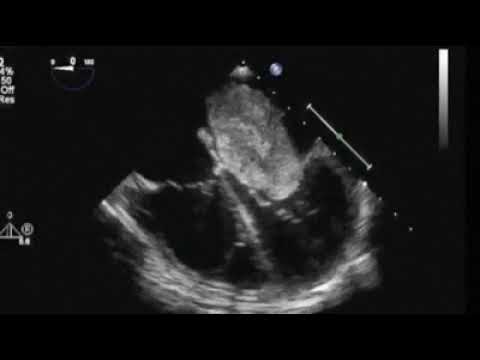

Huge Right Atrial Melanoma

Atrial Myxoma in Echocardiography || Dr. Shankar Dey